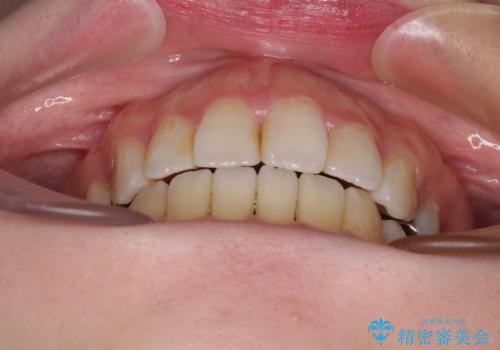

出っ歯と奥歯の欠損 ワイヤー矯正とインプラント治療

- 口元の突出感と奥歯の欠損を気にして来院された患者様です。

口元の突出感改善には、上下左右の第一小臼歯4本を抜歯し、奥歯の欠損部には矯正治療の途中でインプランを埋入していくこととしました。

矯正治療の後半にインプラント埋入を行うことで、トータルの治療期間を短縮することができました。